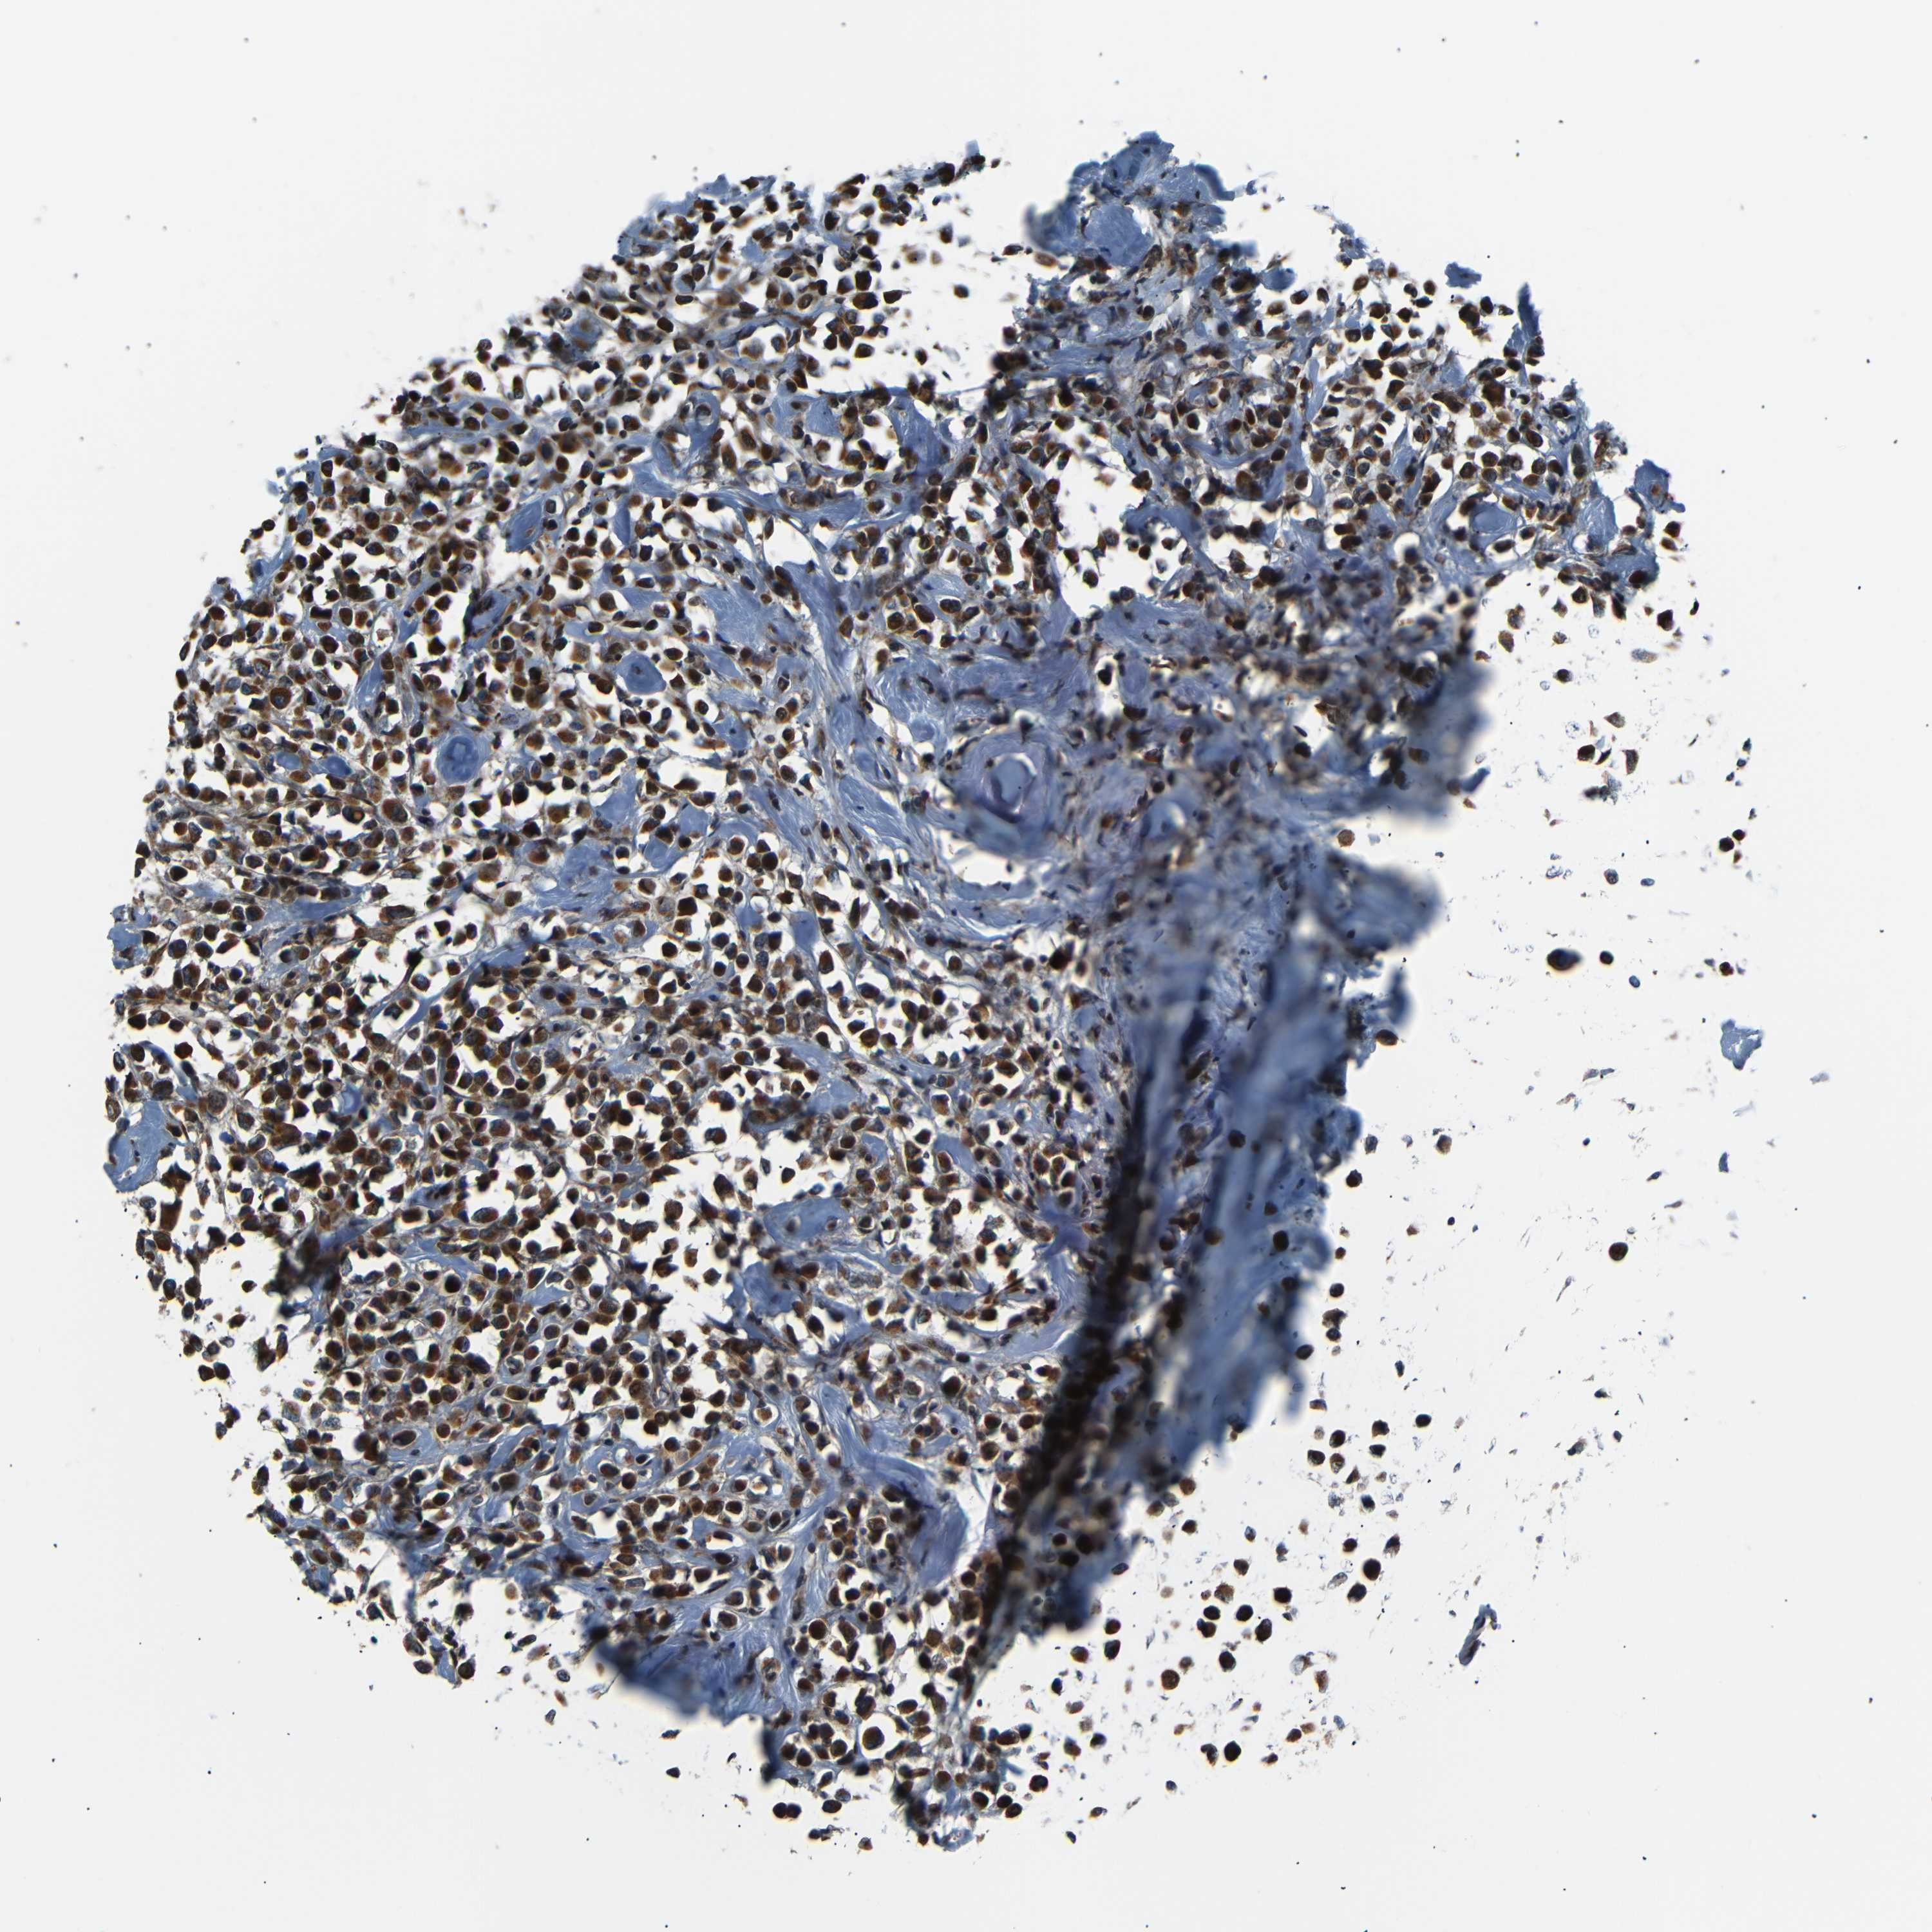

BRCA TCGA BRCA VALIDATION PROTEIN EXPRESSION

ANTIBODIES

AND

VALIDATION